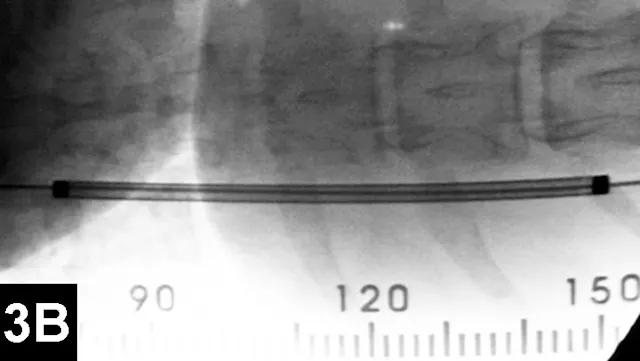

Figure 2A: Serial lateral positive contrast urethrocystograms in a dog with a malignant urethral obstruction secondary to a prostatic tumor.

Maximal urethral diameters measured using a colonic marker catheter to adjust for radiographic magnification.